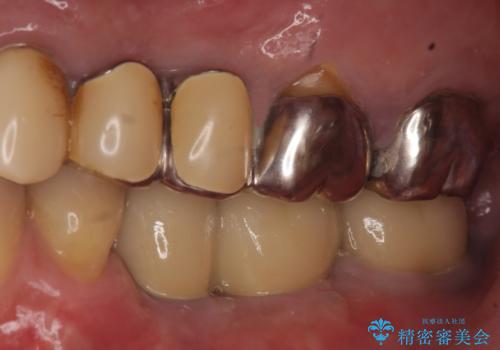

- 左下奥歯が虫歯で抜歯になってしまったため、インプラントにしたいといらっしゃった方の症例です。

欠損部位である左下5、6番目にインプラントを埋入し、オールセラミッククラウンによる補綴を行いました。

左下7番目は再根管治療を行い、オールセラミッククラウンによる補綴を行いました。

オールセラミッククラウンについて

今回用いたオールセラミッククラウンはジルコニアフレームという白い素材の上にセラミックを盛っているため、審美性が非常に高いのが特徴です。

また、ジルコニアは人工ダイヤモンドの材料にも使われているほど高い強度を持っており、そのためオールセラミッククラウンは審美性だけでなく、奥歯やブリッジの補綴も可能とするクラウンです。